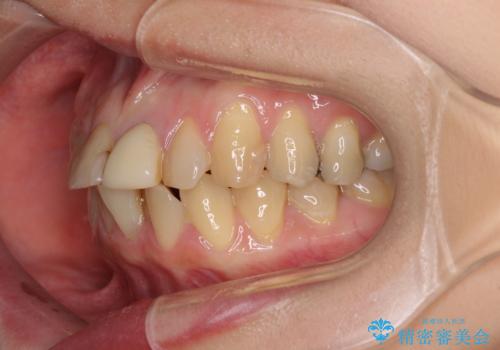

前歯のデコボコをワイヤー矯正できれいに整える

- 前歯のデコボコと変色した前歯を気にして来院された患者様です。

抜歯矯正により口元を引っ込めることも検討しましたが、特に口元の突出感は気になっていないとのことで、非抜歯にてワイヤー装置で矯正治療を行うこととしました。

気になっていた前歯の変色も、矯正治療後にオールセラミッククラウンにて補綴治療を行うこととしました。

舌の突出癖により治療期間中に開咬となり、治療が長引きましたが、口元も治療前よりも引っ込めることができ、すっきりとした仕上がりとなりました。